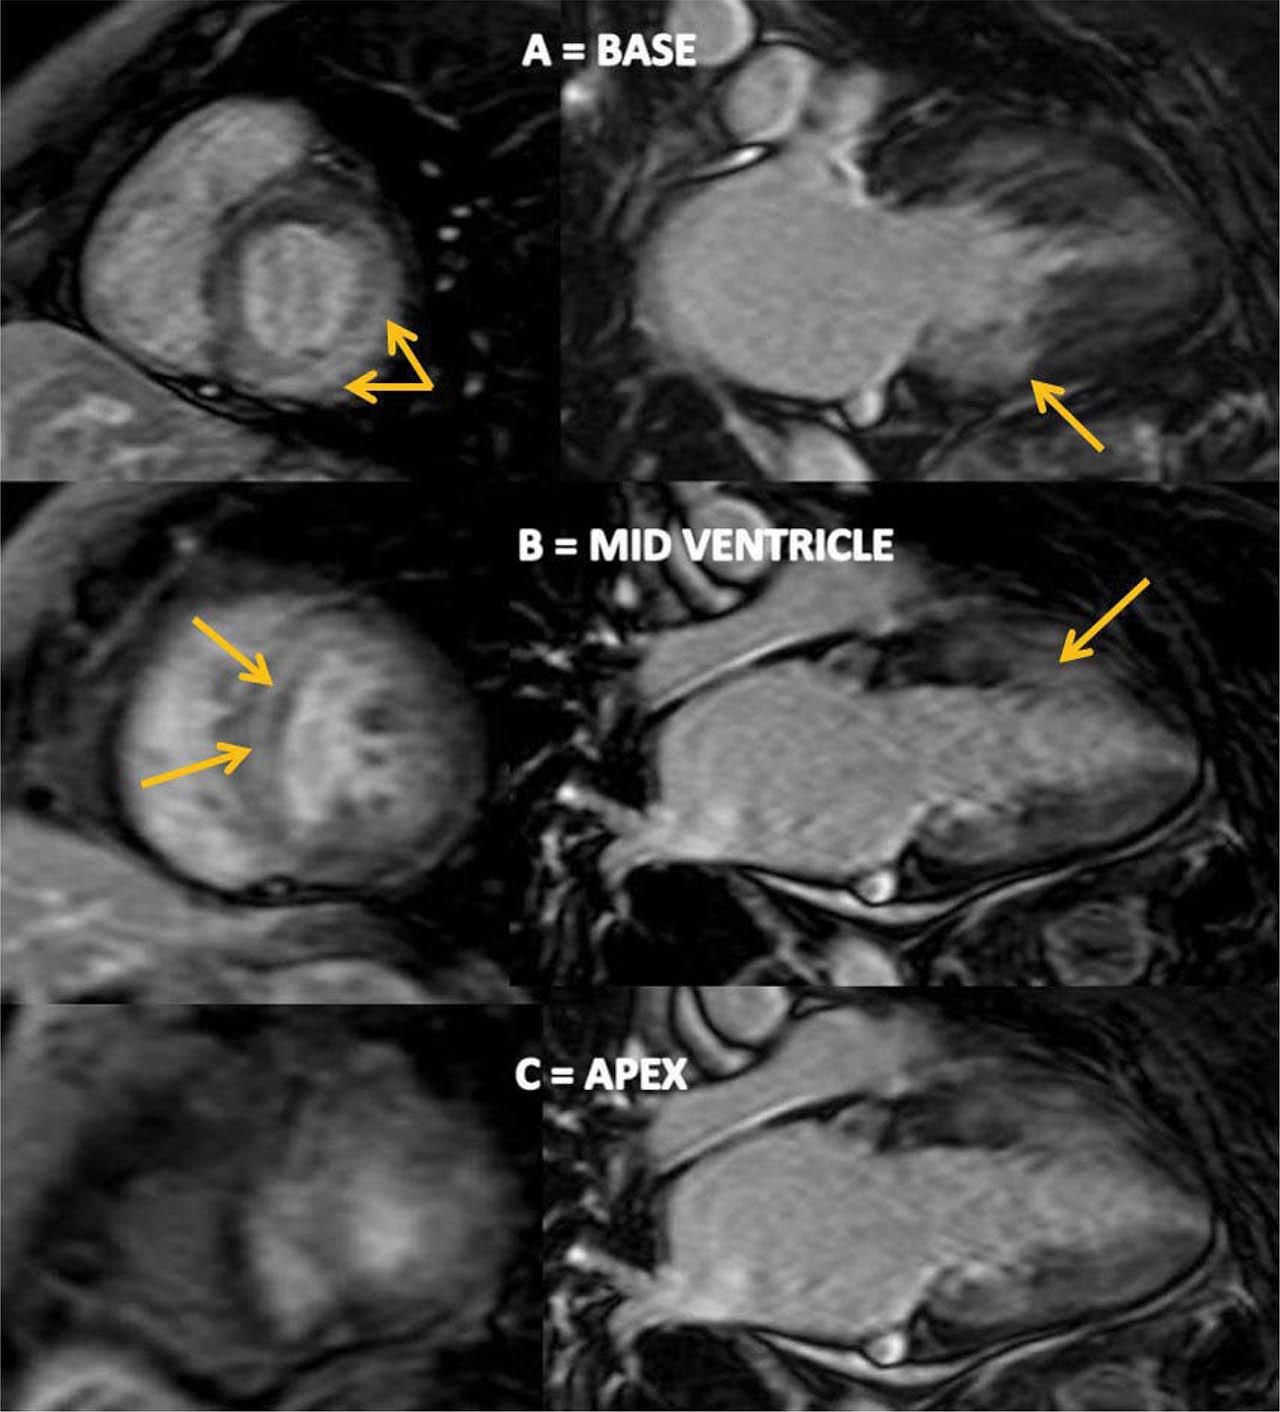

Figure 3